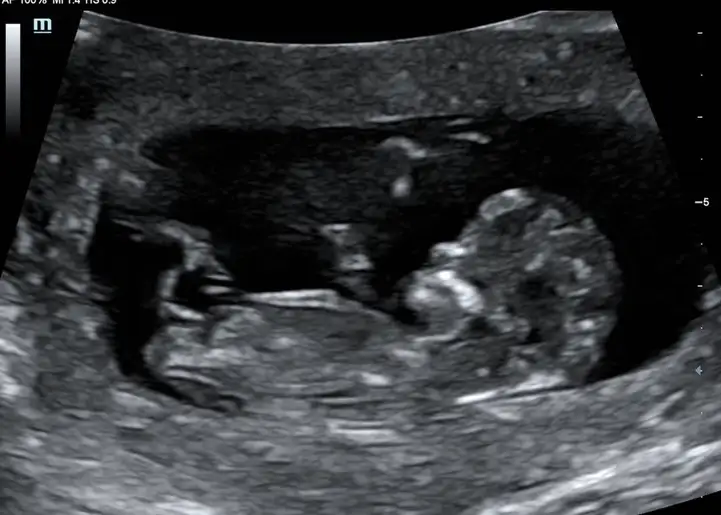

Erkek demiştim erkek diyorumAlttan görüntü sağda solda bacakları ortada pipisi gibidr erkeğe benziyor dedi ama siz ne dersiniz 12+1Eki Görüntüle 2678312

Kız gibi sanki emin olamadimBende cok merak ediyorum bakabilirmisiniz

Erkek gibiKizlar benim bebegimede tahminde bulunurmusunuz rica etsem

Eki Görüntüle 2677696